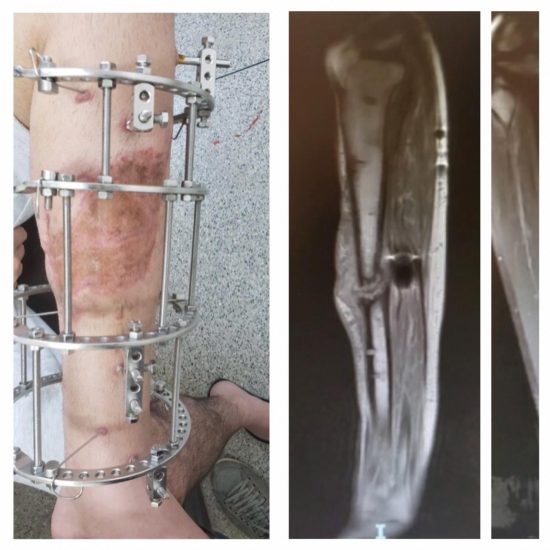

Em abril de 2019, Thiago protagonizou um acidente, na BR 101, enquanto voltava do trabalho. Um caminhão colidiu com o jovem, que conduzia uma motocicleta, o que resultou em uma fratura exposta da tíbia esquerda. Após realizar o tratamento no Sistema Único de Saúde (SUS) e utilizar por nove meses o fixador externo de Ilizarov, conhecido popularmente como gaiola, o rapaz pensou que havia se recuperado. Contudo, dias após a remoção do aparelho, exames médicos constataram que o osso apresentava uma refratura, por não ter se consolidado completamente.

A causa do problema é a osteomielite, uma infecção que tomou 16 cm do osso. Sem plano de saúde e com urgência demais para aguardar o tempo exigido pelo SUS, o jovem resolveu criar uma vaquinha online e contar com a solidariedade. “Eu busquei tratamento no SUS, mas quanto mais tempo passa, mais a infecção se espalha. Por isso decidi criar a vaquinha, com o dinheiro eu pretendo realizar a cirurgia na rede particular”, explica.